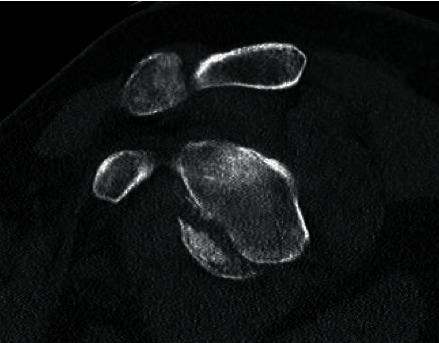

Two elderly males presented with traumatic shoulder dislocation and bony Bankart fracture consisting of greater than 25% of the glenoid width. Due to several concomitant factors such as polytrauma, activity level, rotator cuff pathology, optimization of comorbidities, risk of complications, and potential for revision surgery, the patients were treated with reverse shoulder arthroplasty (RSA).

两名老年男性患者因创伤性肩关节脱位及骨性Bankart骨折就诊,骨折累及范围超过肩胛盂宽度的25%。由于存在多处创伤、活动水平、肩袖病变、合并症的优化、并发症风险以及翻修手术可能性等多种伴随因素,这两名患者接受了反式肩关节置换术(RSA)治疗。